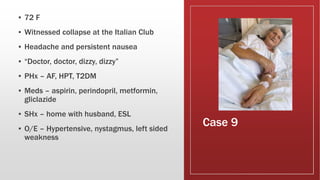

This document discusses various cases of collapse and syncope. It defines collapse as transient loss of consciousness with loss of postural tone and full recovery. Syncope is defined as loss of postural tone with or without loss of consciousness and full recovery. It then discusses the multiple potential causes of collapse and syncope including toxicological, cardiac conduction abnormalities, structural cardiac issues, autonomic dysfunction and more. It then goes through 9 case examples, discussing important questions to ask, potential tests and interventions for each case.